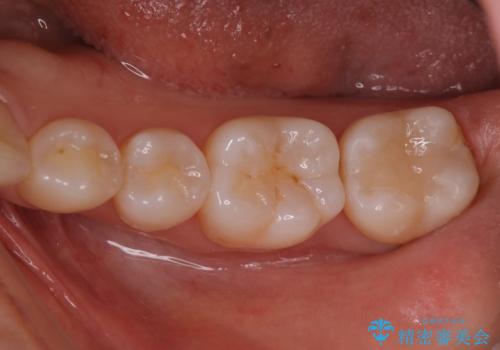

また矯正後、患者様の希望で

メタルインレーをセラミックインレーにやりかえさせていただき、さらに綺麗に仕上がりました。